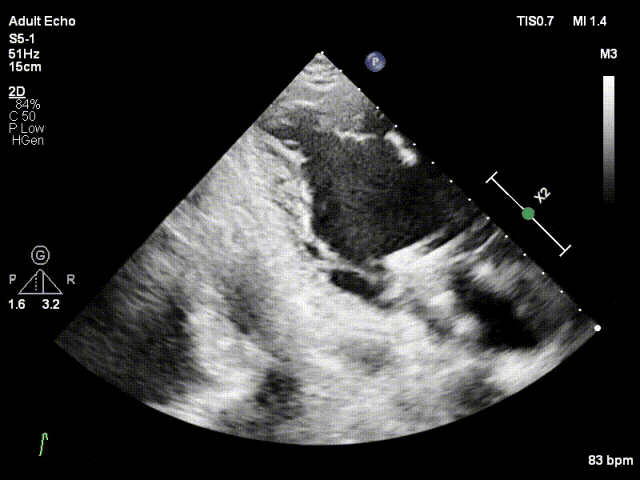

对应策略

术前张小勇教授、段鹏教授团队与陈样新教授、邓冰清教授经充分沟通及分析,决定术中在2区植入一枚长宽(XW0612)型号DragonFly™二尖瓣夹,夹闭后评估残余脱垂及反流决定是否置入第二枚夹子。术中房间隔穿刺高度3.5cm,于2区植入一枚长宽(XW0612)夹,术中患者经食道超声影像质量差,进入瓣下后无法看清前后叶,采用经食道超声结合经胸超声进行瓣叶捕获,术后反流降至轻度,跨瓣压差1mmHg,肺静脉逆流消失。

TTE下捕捞瓣叶

瓣叶捕获,Bouncing明显